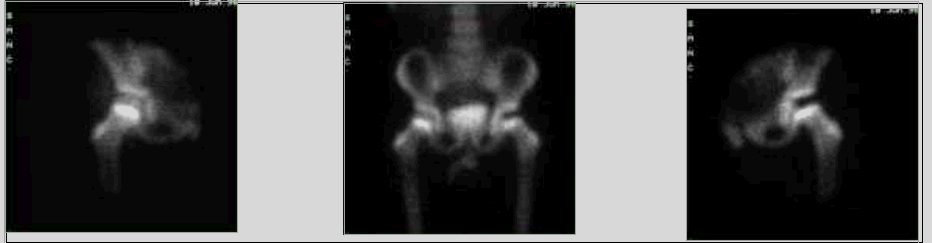

Images scintigraphiques de l’ostéochondrite primitive de la hanche

Illustration 10 : Aspect scintigraphique de l'ostéochondrite (d'après [3]).

Illustration 11 : Scintigraphie : trou de fixation à gauche (d'après [3]).

Illustration 12 : Scintigraphie : trou de fixation à gauche.

Retour sommaire

Illustration 10 : Aspect scintigraphique de l'ostéochondrite (d'après [3])

Illustration 11 : Scintigraphie : trou de fixation à gauche (d'après [3])

Illustration 12 : Scintigraphie : trou de fixation à gauche